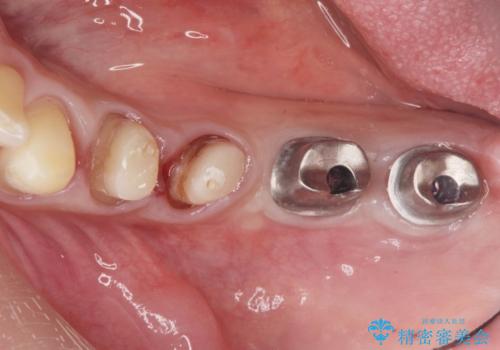

銀歯を外し、インプラントを入れたい

- 「治療途中の歯を治したい。この際、銀歯も全て外したい。インプラントも入れてしっかり噛めるようにしたい。徹底的に歯の治療をしたい。」

と総合的な治療を希望され来院されました。

ここの歯の状態を精密に検査し、根管治療、セラミック治療、インプラント治療を含む総合的な歯科治療を計画します。